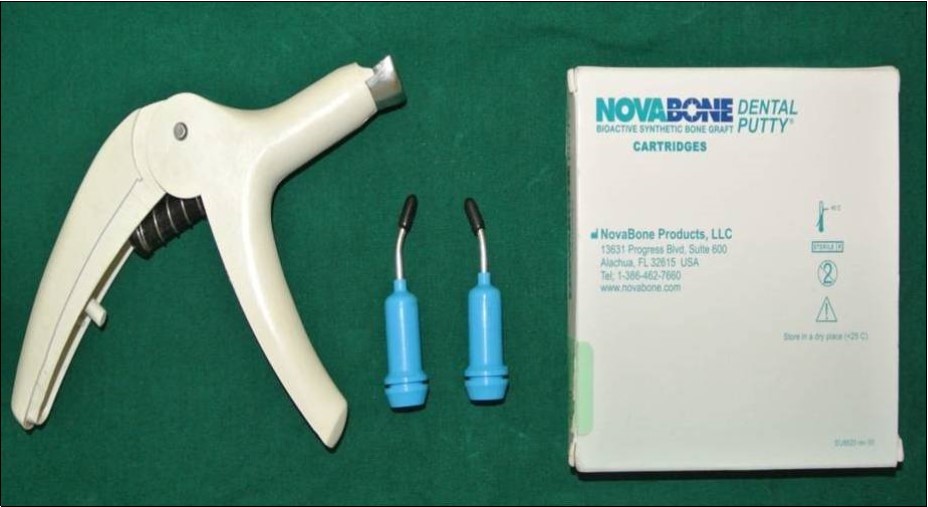

A total of 20 sinus augmentations were carried-out in 17 patients satisfying the criteria (inclusion and exclusion) requiring placement of implants in atrophic maxilla and in other situations of anatomic constraints. The patients were informed about the study including the use of the synthetic graft material and their approval was sought before their inclusion into the study. A written consent was obtained from each of the participating patient. After a detailed history and a thorough clinical examination, including systemic and regional/local examination, patients were taken-up for the sinus augmentation. The type of sinus augmentation procedure, direct or indirect, was decided based on the pre-operative residual bone height evaluated radiographically. The residual bone height was recorded using CBCT scans and a computer based software where the measurements were made from the crest of the ridge till the sinus floor lining. Apically tapered, commercially pure titanium implants (Life Care Devices Private Limited, Mahim, West Mumbai, India) (Figure 1a,b) were used with sinus osteotomes (Figure 2) and associated reamers (Figure 3). The length of implants used were 8, 10 and 11.5mm while the diameter used were 3.5, 4.0 and 5mm. The graft material used was calcium phosphosilicate (CPS) putty (Nova bone dental putty, Novabone products, Alachua, Fla) (Figure 4) in quantities ranging from 0.5cc to 2cc. It is a pre-mixed moldable material consisting of four components including two bioactive phase components, a 55% standard CPS particulate and a 14% CPS smaller particulate in addition to 12% polyethylene glycol additive phase and 19% glycerine binder phase. Bioactivity is initiated immediately upon implantation. The smaller CPS particles release calcium and phosphorous ions into the area while the binder material gets absorbed over a period of a week exposing the larger CPS particulates to blood. In calcium phosphosilicate, the particle sizes are in micrometer size range of 90-710 micrometer range, irregular, in both size and shape. According to Moore et al, in 2001, bioactive glass granules are more quickly reabsorbed than hydroxyapatite, thus, allowing a much more precocious new bone formation in the repair of bone defects.7 On them, osteoblasts show several cytoplasmic processes, pseudopodia, compact appearance, and disorderly dorsal surface, which is characterized by a high cell membrane activity. Therefore, as to the adhesion and close contact between osteoblasts, bioactivity is considered crucial to the development of new bases for bone tissue bioengineering. Its use in various fields, due to its excellent biocompatibility and its physical and chemical properties, has encouraged studies on the feasibility of implant coating, so as to obtain better biologic fixation, and also as a carrier of osteo-inductive substances such as bone morphogenic proteins and other growth factors.8, 9 Other authors also demonstrated the effectiveness of bioactive glass as they improved the osseo-integration of coated implants providing better bone support and presenting with an increased stability when compared to the machined implants.10

Figure 4.calcium phosphosilicate (CPS) putty (Nova bone dental putty, Novabone products, Alachua, Fla) used as graft material;

Under complete aseptic conditions, local anaesthesia with vasoconstrictor (2% lignocaine with 1:80,000 adrenaline) was used to obtain ample anaesthesia at the surgical site. Direct sinus membrane elevation was carried-out in cases with residual bone height of <5mm where a lateral spherical bone window was created using the lateral sinus approach technique. No membrane covering was used to cover the defect. (Figure 5a-f) Indirect sinus membrane elevation followed by implant placement was done in cases with residual bone height of >5mm but <9mm. (Figure 6a-h) Alloplastic graft material was then dispensed using the gun and cartridge form either through the bone window or through the crestal osteotomy site before achieving the primary closure. The patients were assessed clinically at immediate post-operative, 1 week, 1 month, 3 months and 6 months follow-up recalls post-operatively. Radiographic assessment for bone height was done pre-operatively and at 6 months follow-up recall post-operatively using Cone Beam Computer Tomography scans. In this comparative study, the measurements were tabulated and statistically analysed to evaluate the difference in increase in bone height between direct and indirect sinus augmentation procedures radiographically.